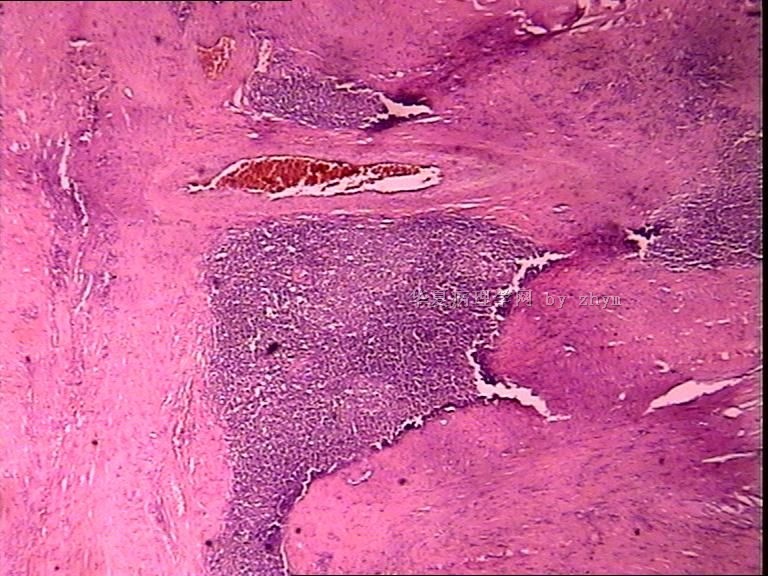

膀胱肿物

性别:

男

年龄:

46岁

标本名称:

简要病史:

肠梗阻入院

肉眼检查:

肿物位于膀胱尖部,腹膜外,约4x3cm,内含胶冻样物质,壁厚0.1-1.5cm。

图1